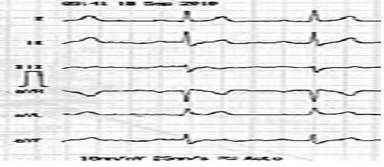

Paciente, sexo masculino, 45 anos de idade, sem patologias prévias, totalmente assintomático, sem histórico familiar positivo para quaisquer patologias cardiovasculares, foi ao médico, pois estava com uma hérnia inguinal. Seu médico solicitou um eletrocardiograma, apresentado em seguida.

Com base nesse caso clínico, e considerando os conhecimentos médicos a ele relacionados, julgue os itens a seguir.